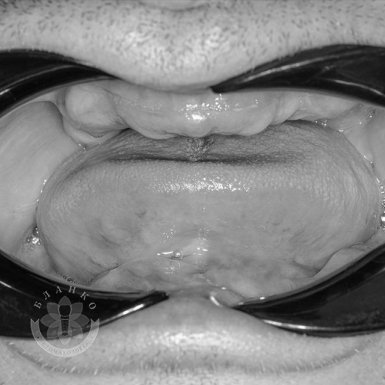

Зубна імплантація — це сучасне та надійне рішення для відновлення втрачених зубів. У стоматологічній клініці Бланко ми пропонуємо імплантацію зубів «під ключ», що означає повний комплекс послуг — від діагностики до встановлення коронки, без прихованих платежів та несподіваних витрат.